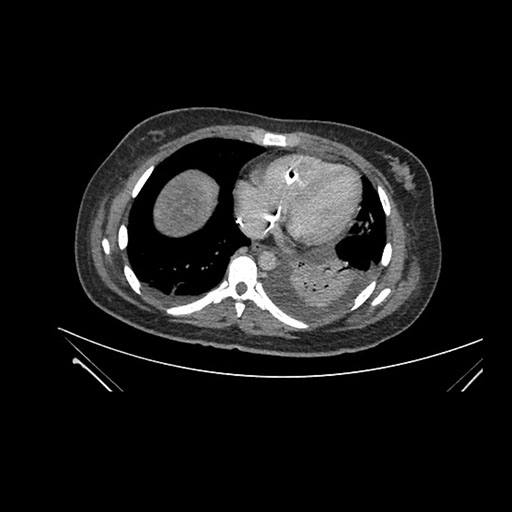

Imaging Analysis

Look through the patient's CT scan to identify any areas of concern for the necessary procedure.

Coronal Arterial

Based on initial findings, which issue(s) would you be most concerned about?